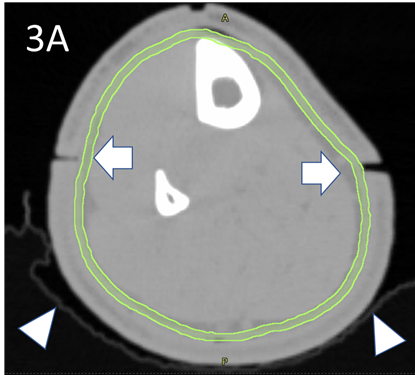

Wires were placed over all RO marks to capture these positions on the CT scan. The latter was done at 2mm increments. Bi-valved 3DPB was then ordered and was fitted at a second simulation session. The RO then contoured the clinical target volume (CTV) and planning target volume (PTV)8 according to the national protocol7 using MIM MaestroTM planning software. A contour volume called “Skin Avoid” was created by having a structure that extended on all the slices on which there was a PTV. This volume was made by the RO and was 1.5cm inside the PTV into the centre of the leg. The Skin Avoid structure was prescribed to receive a dose less than a mean of 25 Gy. See Figure 3.

Figure 3A The RO drew the contour of the epidermis as the CTV on the planning CT, here in light green. This is usually 2-4 mm in thickness. The white triangles denote the snugly fitting vac bag. White arrows denote the joints in the 3DPB at baseline.